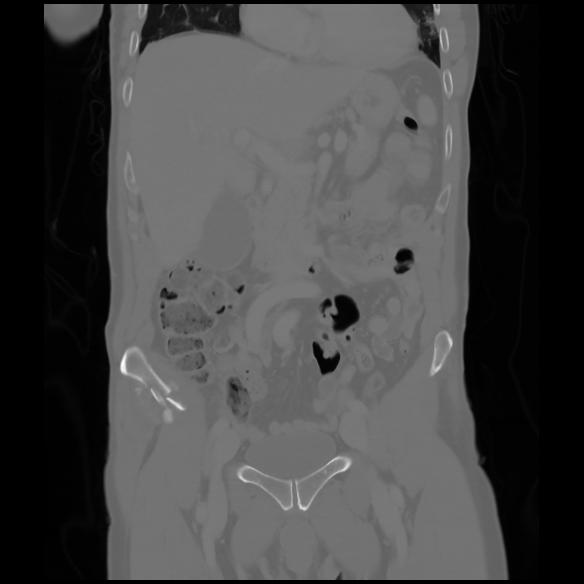

6 CUERPO,CE,Coronal,3.000,CUERPO,Coronal,